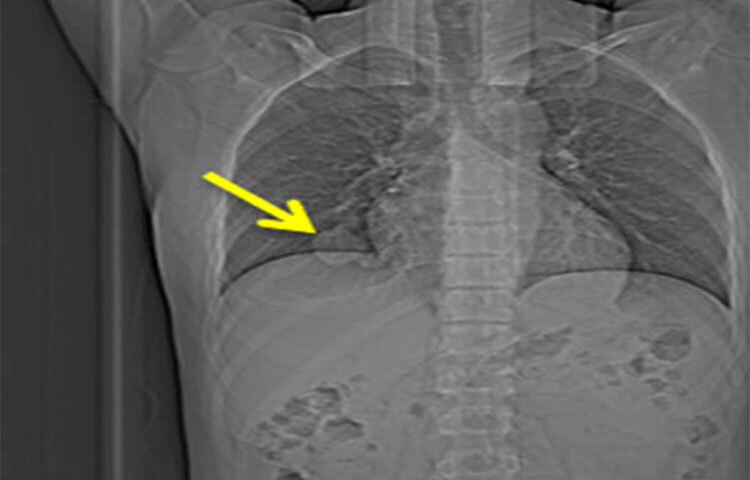

চিকিৎসকরা বারবার ধূমপান ছেড়ে দেওয়ার কথা বললেও যারা এখানো ধূমপান করছেন, পাশাপাশি যারা বেশি পরিমাণে ধূমপান করেন তাদের বছরে অন্তত একবার কিছু পরীক্ষা আছে তা করানো উচিত। জেনে নিন কোন কোন পরীক্ষাগুলো করাতে হবে।